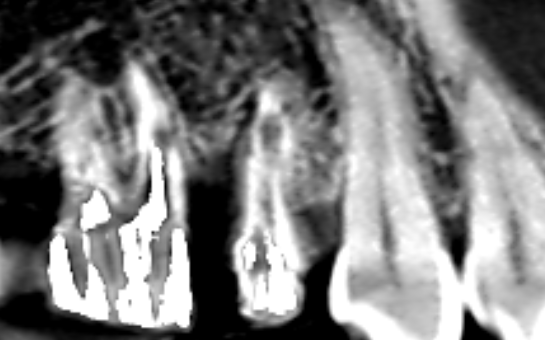

マイクロスコープ歯周再生療法を行ったケース。歯の周囲の骨が回復している。